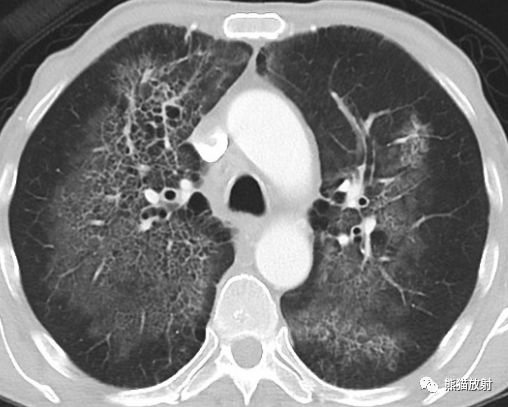

肺部之“蝙蝠翼征”

蝙蝠翼征 或 蝶翼征

蝙蝠翼样肺部影是指双侧肺门周围的阴影。

通常在正位胸片上用来描述相关表现,也可指胸部CT上的表现。